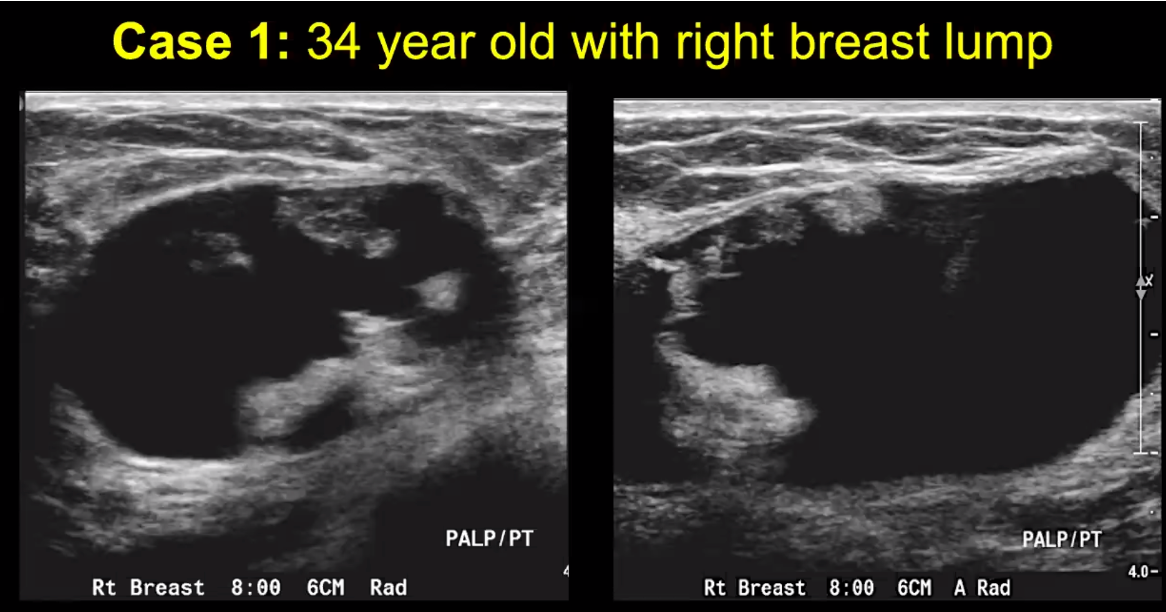

complicated cyst

30% chance of malignancy

BUT…in this case on mammo there was egg shell/rim calcifications. So this was a case of fat necrosis which can mimic malignancy